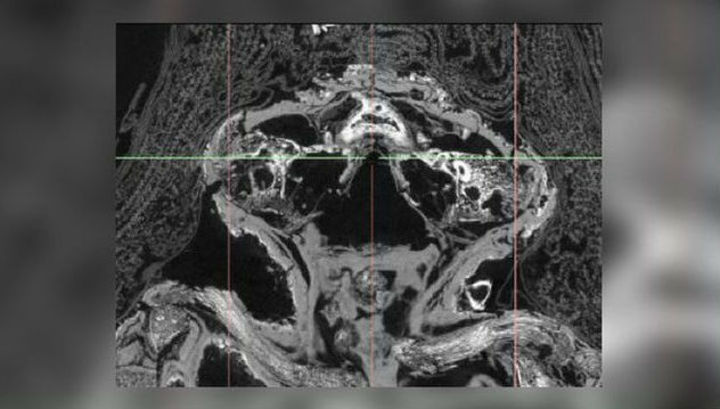

Спустя время Нельсон возглавил группу учёных, исследовавших объекты при помощи микро-КТ сканирования — технологии, позволяющей получать изображения с высоким разрешением мумии, не открывая при этом её погребальный материал. И здесь-то учёные не поверили своим глазам.

Оказалось, что останки принадлежали вовсе не птице, а сильно деформированному мертворождённому зародышу человека, гестационный возраст которого на момент смерти составлял от 23 до 28 недель.

Сканирование выявило нормально сформированные кости пальцев рук и ног, а также серьёзную деформацию черепа. У зародыша также была расщелина нёба (волчья пасть) и врождённая расщелина губы.